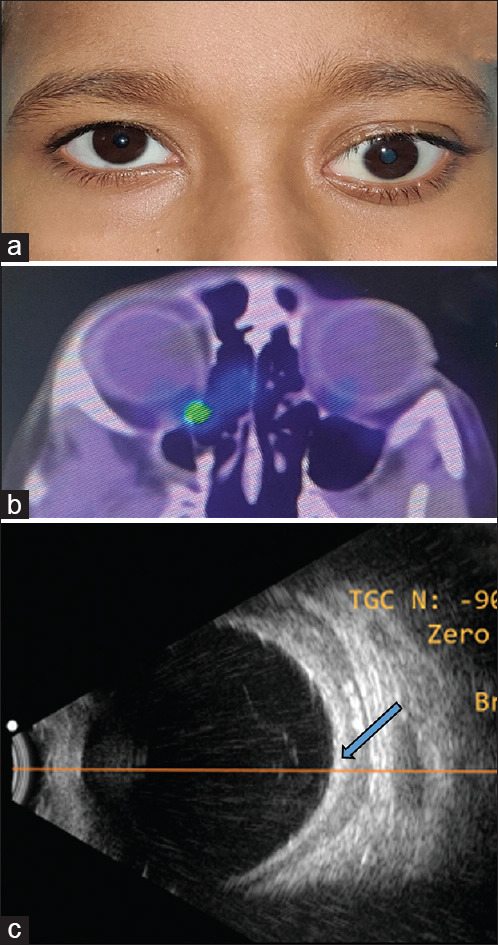

A 5-year-old boy presented with gradually progressive painful proptosis of the left eye for 5 months. He had an incidental testicular swelling for which he underwent high inguinal orchidectomy and histopathology showed atypical lymphoid cells. His vision was 6/6, N6 in the right eye, and no perception of light in the left eye. Left eye examination revealed an inferior dystopia and total ophthalmoplegia with corneal exposure changes. A computerized tomography scan showed an isodense mass molding around the globe. An incision biopsy from the subconjunctival mass showed atypical large lymphocytes on histopathology which on immunohistochemistry confirmed a diagnosis of precursor B-cell lymphoblastic lymphoma (B-LBL). Bone marrow aspiration and biopsy were normal. The patient was started on oral steroids and high-risk acute LBL chemotherapy protocol to which he showed excellent response. Precursor B-LBL is a rare neoplasm of the pediatric and adolescent age group. A total of 22 cases involving the orbit have been reported to date of which 17 belonged to the pediatric age group. Early detection and prompt initiation of multiagent chemotherapy have shown good survival rates in these patients.